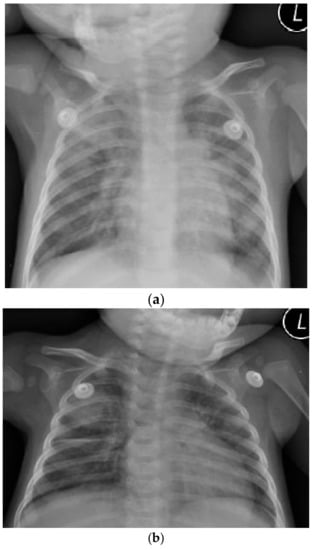

TB Presenting as Recurrent Pneumonia in a HIV-Infected Infant in Central Viet Nam

1. Case Report